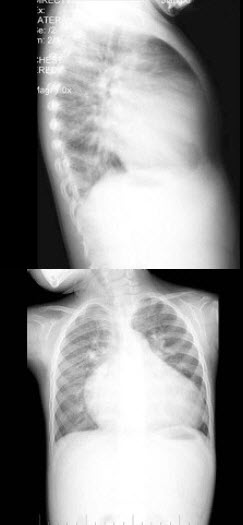

26、单项选择题

女,12岁,脊柱侧弯畸形,双下肢长短不一,结合图像,最可能的诊断是()

A.骨纤维结构不良

B.骨巨细胞瘤

C.内生软骨瘤

D.非骨化性纤维瘤

E.Paget病